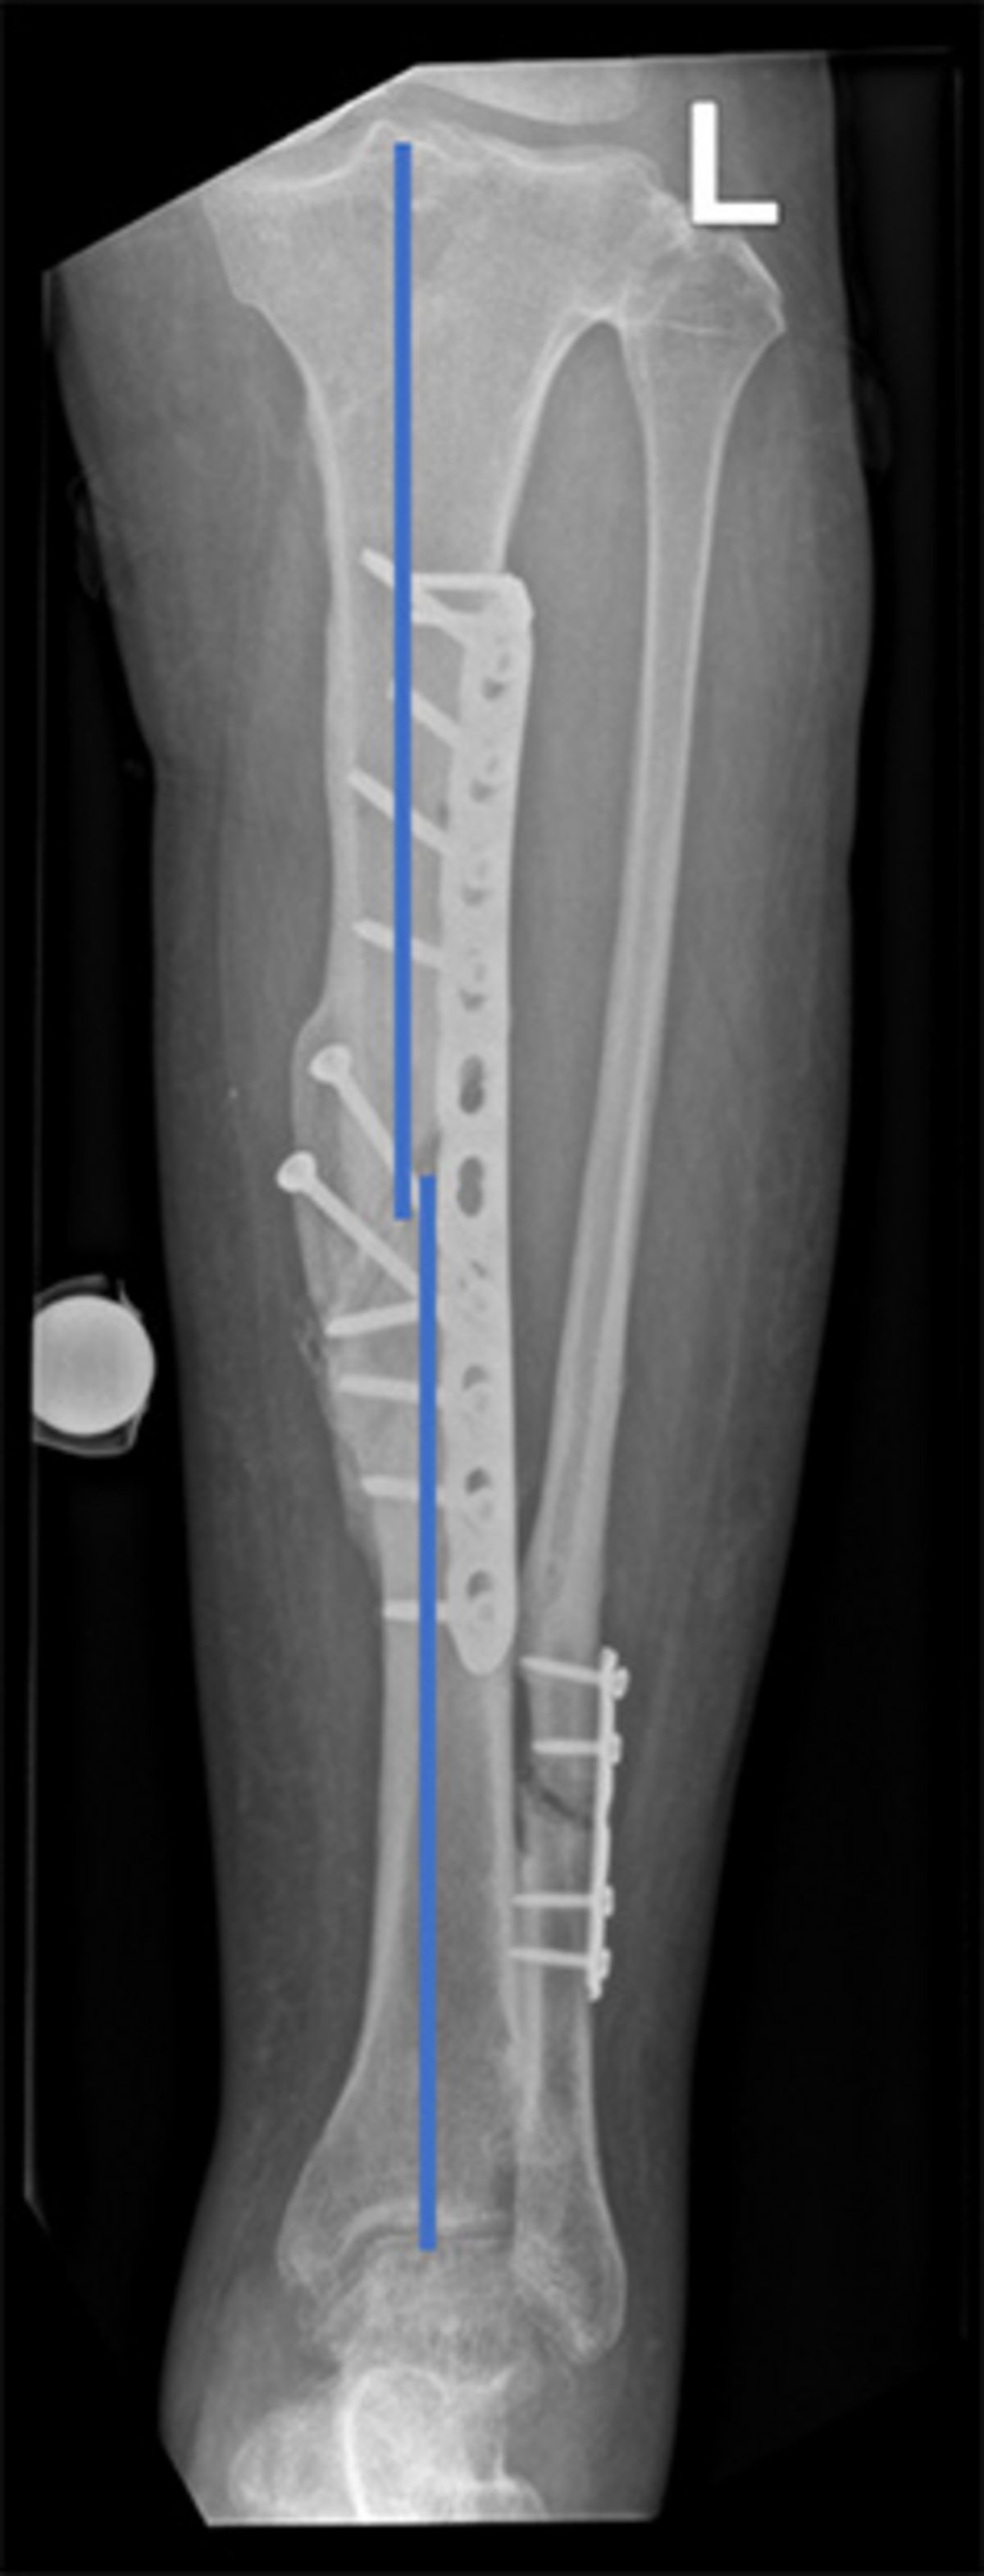

Eine Fehlstellung kann nur durch eine Operation korrigiert werden. Die Planung der Korrektur erfolgt klassischerweise anhand zweier Röntgenbilder – von vorne und von der Seite. Um den Knochen wieder in seine möglichst ideale Form zu bringen, werden häufig sogenannte Knochenblocks (aneinanderhängendes Knochenstück) eingebracht oder entfernt. Ist die Fehlstellung aber in beiden Ebenen (von vorne und von der Seite) oder zusammen mit einer Rotationsfehlstellung, ist eine ganzheitliche, dreidimensionale Korrektur mit diesem Verfahren nur eingeschränkt möglich.

Unser eigens dazu entwickeltes Computermodell berücksichtigt jedoch die Dreidimensionalität der Deformität. Unsere Software ermöglicht zudem die genaue Planung der Korrektur anhand des anderen Beins *, *. Häufig kann damit die Fehlstellung korrigiert werden, während weniger oder gar kein Knochen eingebracht oder entfernt werden muss. Der Grund dafür ist die genau berechnete Ebene, in welcher der Knochen durchtrennt und gedreht wird.

Für eine äusserst genaue operative Umsetzung der Korrektur wird diese nicht freihändig durchgeführt, sondern anhand von Schablonen, die exakt auf den Knochen der Patientin oder des Patienten angefertigt wurden (patientenspezifische Schablonen). Um den Knochen in die richtige Position zu bringen und zu halten, werden weitere Schablonen eingesetzt. Diese halten den Knochen zudem genau in der gewünschten Position, bis er mittels Schrauben und Platten fixiert wird.